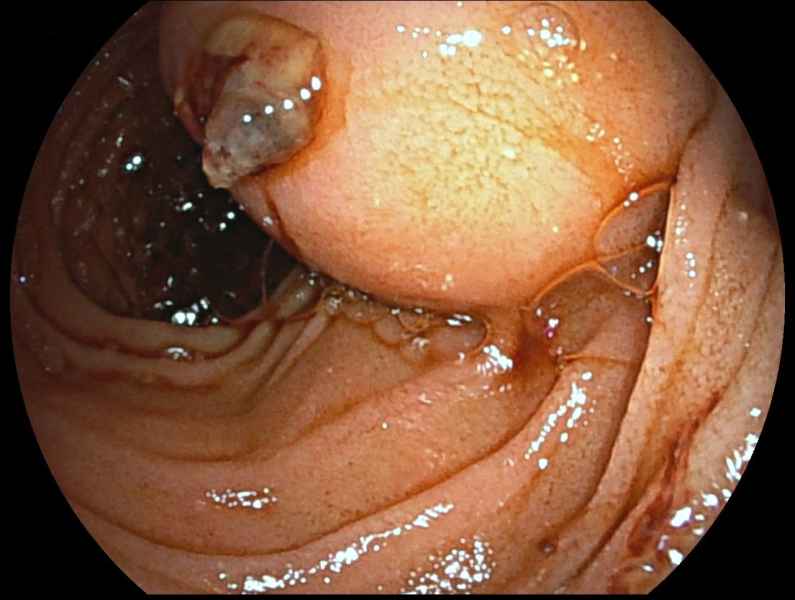

Gallstone ileus: A rare cause of bowel obstruction in a liver transplant patient

Fotografia